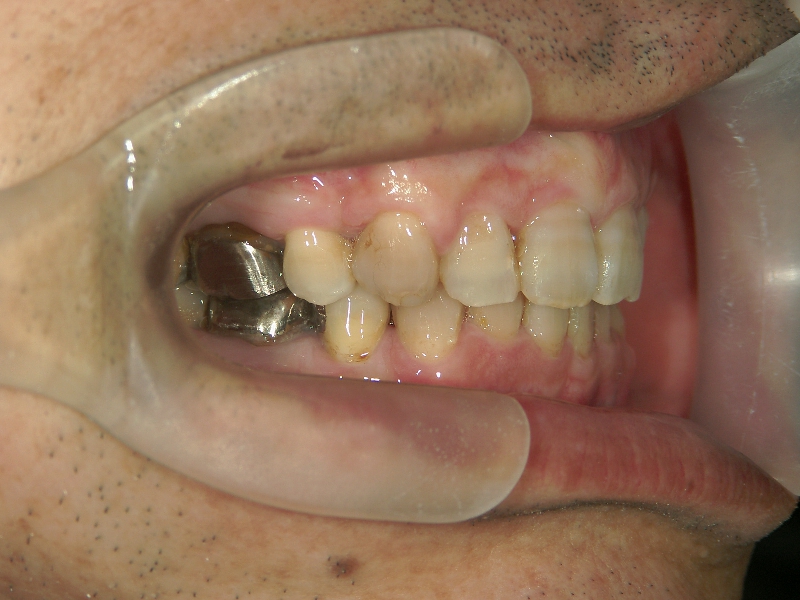

no.22_8175_治療前_右.jpgno.22_8175_治療前_正面.jpgno.22_8175_治療前_左.jpg

矯正歯科 治療前 右上4番、左右下4番 計3本抜歯し、叢生を改善